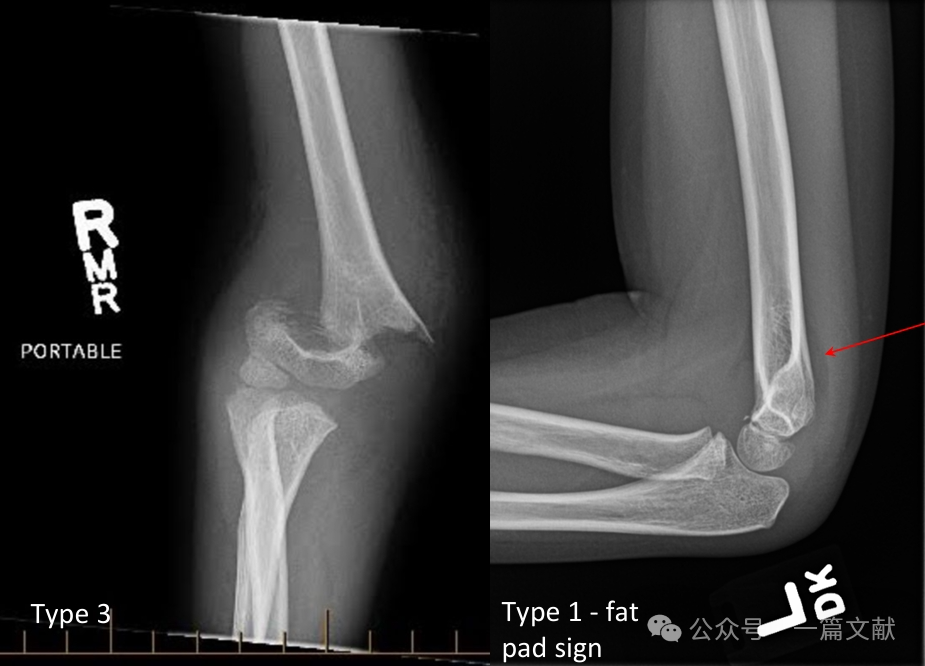

II. Imaging Studies: Plain radiographs are usually sufficient. AP and lateral views of the elbow are required. Obtain ipsilateral forearm/wrist radiographs to assess for associated injuries. Evaluate for the posterior fat pad sign in nondisplaced fractures (indicated by arrow).

* Posterior Fat Pad Sign: Highly suggestive of fracture (whereas an anterior fat pad sign can be seen without fracture).

* Type 1: Nondisplaced.

* Type 3: Displaced fracture with disruption of the posterior hinge.